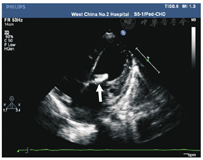

本组28例IE患儿中,89.3%(25/28)IE患儿存在心内赘生物,包括多部位受累2例(8.0%,2/25),分别为右房壁、肺动脉瓣、三尖瓣受累1例,以及主动脉瓣、二尖瓣受累1例;其余23例患儿均为单一部位受累。这25例IE患儿的心内赘生物平均大小为10.7 mm×9.0 mm。心内赘生物以二尖瓣受累最多见,占40.0%(10/25)(图1),二尖瓣前叶及后叶受累各占20.0%(5/25);其次为肺动脉壁近动脉导管开口处、主动脉瓣,各占16.0%(4/25);其后依次为三尖瓣、肺动脉瓣各占12.0%(3/25),右房壁占4.0%(1/25)。